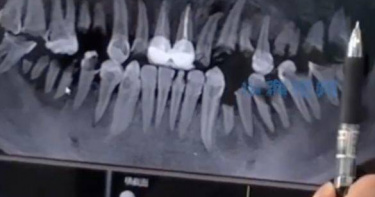

大陸一名網友近日在社交平台發文稱,「拔掉的智齒又長出來了」,引發關注與討論。該貼文的評論區中,多數聲音對此說法表示懷疑,猜測「之前是否拔錯了牙」,又或是「多生牙」。此外,還有一些網友分享自己的類似經歷。《九派新聞》報導,貼文發布者付女士(化姓)透露,她於2018年因牙齒發炎到診所拔了左下方一顆智齒,並將拔掉的牙齒帶了回家,自己清楚地記得,當時拔牙後,牙齒留了一個洞,每次吃東西都會塞牙,需要及時沖洗牙齒,隨著牙齒逐漸長出,塞牙和沖牙的次數也有所減少。付女最近牙痛得厲害,去口腔醫院牙科拍片,竟發現智齒數量仍是早期拔牙前的四顆,她感到難以置信,先後與兩位醫生再三確認,結果依舊如此。當醫生建議拔智齒時,她提到早年拔過智齒的經歷。據付女轉述,當時醫生始終懷疑她沒有拔過,即便她翻出此前的拔牙照片與有關社交動態時,醫生仍持疑。據了解,付女當年除了拔牙,還補了左上方一顆牙齒,而補牙旁邊也有一顆智齒。如今,她補的牙已經掉落,拔掉的智齒疑似又長出。她稱,最近牙疼的位置正是「新長出智齒」的地方。此次就診後,付女打算等不痛之後再去拔牙。智齒拔掉後究竟是否會再長出?華中科技大學同濟醫學院附屬協和醫院口腔種植科主任、教授、主任醫師楊成表示,本身不長智齒是可能的,但在同一個位置,拔掉智齒後再長出智齒是不可能的,「要麽沒拔出來,要麽記錯了拔牙位置,新長出的牙齒不會是之前拔過的智齒。」此外,醫師提到另一種可能性,極少數情況下,智齒旁邊的牙,因被智齒擋住未長出來,在拔掉智齒後,旁邊的牙有可能長出。針對網友猜測「可能是多生牙」,楊成表示,這取決於第一次拔牙時的情況,多生牙一般在前牙區常見,很少在智齒的位置出現,如果智齒旁本身有一顆多生牙,拔掉智齒後,多生牙顯露出來,倒是有可能。

開水才是最健康的飲料!大陸湖北武漢有一名23歲男子,長期把可樂當開水喝,一天至少要喝個2、3瓶才過癮,結果大量喝下可樂,身體機能還沒出現大問題,牙齒率先拉警報,這名男子因為可樂喝太多,除了喝出嚴重蛀牙,牙齒還因為長期被大量飲用的可樂腐蝕,牙齒幾乎全壞光,必須靠大量拔除真牙,再做後續的植牙修復。綜合陸媒報導,大陸這名男子因為出現大量的蛀牙、掉牙,而到武漢協和醫院求診。醫師詢問男子平時的飲食與生活習慣才發現,男子年紀輕輕卻出現嚴重的蛀牙、掉牙,原來是他長期都不喝白開水,只要一口渴就喝可樂這類的碳酸飲料解渴,對牙齒帶來極大殺傷力。負責收治該病例的醫生表示,男子除了前方牙齒,因為曾做過牙冠修復,狀況相對穩定之外,後方的其他牙齒,基本已經因為長時間被可樂這類的碳酸飲品「腐蝕」,大部分都被蛀壞了。醫生表示,可樂裡面有碳酸,很容易和牙齒裡的鈣質發生反應,進而對牙齒產生腐蝕效果。因此建議大家盡量不要喝含糖飲料,若真的想喝飲料,建議喝無糖的飲品,飲用時要妥善控制攝取量,「晚上睡前一定要刷牙,刷完牙就不要再吃東西、喝飲料了。」針對這名喝可樂喝到滿口爛牙的病例,醫生表示,目前只能盡量保留能修復的牙齒,對於那些已經爛到牙齦下方,無法修復的爛牙,只能進行拔除,再做後續的植牙修復了。